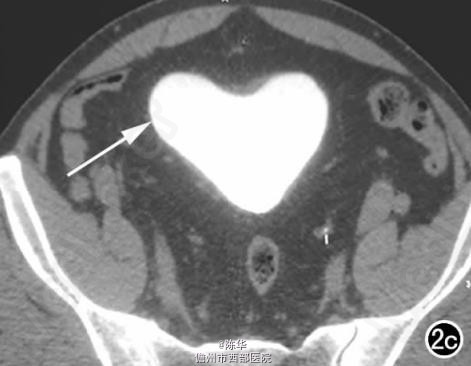

腹部B超示双肾增大,双肾慢性肾病声像;双肾中度积液伴双输尿管上段扩张。 IVPshi双侧输尿管中或下段梗阻。 膀胱造影:经尿道置管后,注射对比剂充盈膀胱,膀胱下半部先充盈,继续灌注对比剂后见膀胱完全显影,膀胱形态异常,呈“倒葫芦状”(图1)。 CT增强扫描行延迟期 MPR重组,见双侧肾盂、肾盏扩张积液;双侧输尿管纡曲、扩张,下端呈鸟嘴样变窄;膀胱变形、体积减小(图2); MRI平扫示双侧肾盂、肾盏扩张积液,双侧输尿管扩张并下端鸟嘴样变窄,盆腔内多量脂肪沉积,分布于膀胱、直肠周围,T1WI、T2WI呈明显高信号,T2WI抑脂像呈稍高信号,膀胱受压变形、体积减小(图3a~c); MRU示双侧肾盂肾盏扩张、积液,双侧输尿管显著纡曲、扩张,下端鸟嘴样变窄,管壁光整,膀胱变形、体积较小、位置抬高(图3d)。